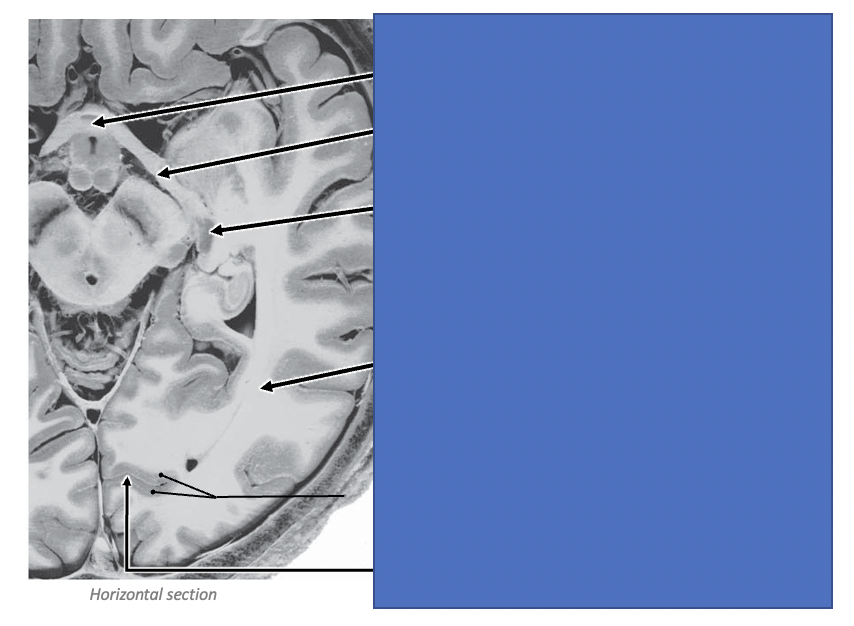

Locate the structures of the visual pathway

Identify the following structures

What is labelled 1-5 in this diagram?